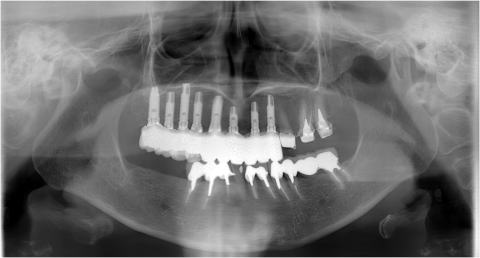

このページに提示してある症例はすべてインプラント治療の未来形

フラップレス・無痛手術を行っております。

上下顎両側臼歯部のインプラント治療

ケース3